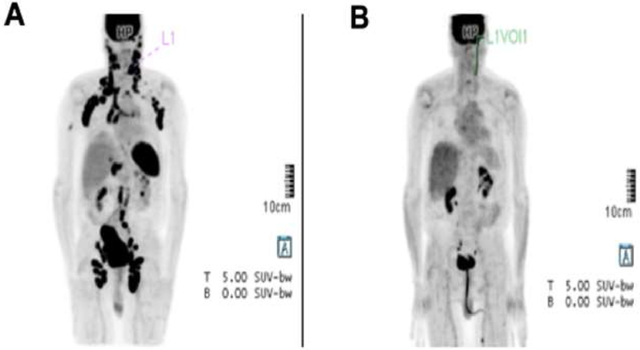

2020年3月,贝勒医学院细胞和基因治疗中心研究人员描述了一项针对复发或难治性(r/r)T细胞恶性肿瘤的自体CD5靶向CAR-T细胞的I期剂量递增研究(NCT03081910)。

CD5是一种泛T细胞标志物,存在于约85%的T细胞恶性肿瘤中。该研究旨在评估CD5 CAR-T细胞对r/r T细胞恶性肿瘤患者的安全性和可行性,作为桥接至异基因造血干细胞移植(allo-HSCT)的手段。

治疗了5例CD5阳性复发或难治性非霍奇金T细胞淋巴瘤(T-NHL)患者,1例血管免疫母细胞性T细胞淋巴瘤(AITL)患者和1例外周T细胞淋巴瘤(PTCL)患者获得完全缓解(CR)。

另1例广泛型AITL患者因出现新的PET阳性病灶(尽管其余病灶消退)被归类为混合反应。该患者接受了第二次CAR-T细胞输注,随后进行了造血干细胞移植,移植后6个月仍保持完全缓解。

这些结果表明,CD5 CAR-T细胞具有安全性,可在经过大量预处理的复发或难治性(r/r)T细胞恶性肿瘤患者中诱导临床反应。